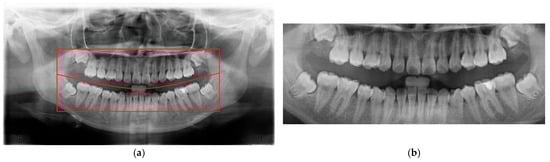

2.2.3. Frame Moving

Two common segmentation approaches exist, with one involving the masking of the target tooth to exclude non-relevant areas, while the other segments the teeth based on their individual contours [24,25]. However, because the identification of impacted teeth requires the contextual presence of at least two adjacent teeth, both segmentation methods were modified accordingly in this study. Through empirical evaluation and implementation, a frame size of 200 × 300 pixels was determined to be the most effective for capturing a sufficient diagnostic region, as shown in Figure 9.

Figure 9. An example of a 200 × 300 image cropped from a PANO image.